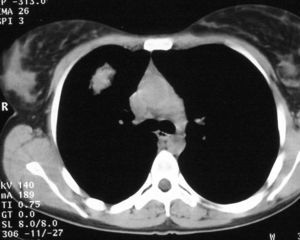

Mujer de 26 años de edad, fumadora de 10 cigarrillos al día, sin otros antecedentes de interés, que consulta por dolor torácico pleurítico sin fiebre, ni otra sintomatología acompañante. Las pruebas de laboratorio fueron normales. En la radiografía de tórax se observó una lesión redondeada de unos 3 cm en el lóbulo superior derecho, parahiliar (fig. 1). Ante la posibilidad de que se tratara de una neumonía redonda, recibió tratamiento antibiótico empírico con amoxicilina-clavulánico, sin cambios radiológicos. Se realizó una tomografía computarizada (TC) torácica sin contraste intravenoso, que mostró un nódulo pulmonar de bordes mal delimitados de 2 x 3 cm en el segmento anterior del lóbulo superior derecho, con tres nódulos satélites adyacentes (figs. 2 y 3). La fibrobroncoscopia fue normal. La citología del broncoaspirado y cepillado bronquial fue negativa para malignidad. Los cultivos para bacterias, hongos y micobacterias resultaron estériles. Se practicó una punción aspiración con aguja fina (PAAF) transtorácica bajo control con TC, obteniéndose material sin evidencia de malignidad. Ante la ausencia de diagnóstico y la imposibilidad para descartar malignidad se realizó una lobectomía superior derecha.

Fig. 2.--Tomografía computarizada helicoidal sin contraste, con cortes de 8 mm a la altura de ventana aortopulmonar, muestra un nódulo sólido de márgenes mal definidos, en segmento anterior de lóbulo superior derecho.